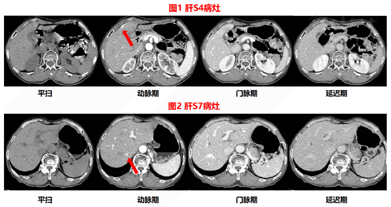

胆囊切除术前CT检查发现肝内病灶,胆囊切除术中病理结果证实S4段病灶为神经内分泌瘤,胆囊切除术后MRI确定剩余病灶,US-MRI容积导航影像融合联合超声造影进行病灶定位、引导、术后评估。

患者,女性,57岁,患者半年前CT提示:1.肝S4包膜下及S7动脉期可见一过性强化,考虑异常灌注,建议动态观察;2.胆囊底壁增厚并强化,考虑胆囊腺肌症可能。1个月前行腹腔镜胆囊切除术,术中发现S4交界处包膜下肿物并切除,现拟进一步治疗。入院查体:心肺腹未见明显异常,专科检查:腹部平坦,可见陈旧手术瘢痕,未见胃肠型及蠕动波,未见浅表静脉曲张。脐部正常,腹式呼吸存在。无液波震颤,无震水音,未触及腹部肿块。全腹腹肌软,无明显压痛及反跳痛,Murphy征阴性。肝脏肋下未触及。脾脏未触及。肾未触及。肝浊音界存在,肝上界位于右锁骨中线第6肋间,移动性浊音阴性,肝区、双肾区无叩痛。肠鸣音正常,无气过水声,未闻及腹部血管杂音。

原发性HNEC与转移性HNEC鉴别相对困难,需依赖全面的检查和长期的随访[9],本例患者初次由增强CT发现肝内病灶,考虑为异常灌注可能,缺乏典型影像学表现,定期常规超声检查中均未发现明显异常。在胆囊腺肌症切除手术时发现肝S4包膜下外突病灶并切除,最终病理学证实为神经内分泌肿瘤,G1期。完善胃肠镜等相关检查,均未见明显异常,初步考虑为肝内原发神经内分泌瘤并肝内多发转移。由于患者极度焦虑,并拒绝手术切除,在综合考虑后,在US-CT/MRI影像融合容积导航引导下微波消融术,但在术后9个月复查时发现胰腺尾部神经内分泌瘤,手术确诊为胰腺神经内分泌瘤,于是考虑本病例为转移性HNEC,造成漏误诊原因是本例胰腺NET早期缺乏典型影像学特征,且实验室检查均为阴性,因此造成漏误诊。也告诉我们在发现其他部位神经内分泌瘤时需要多次仔细全面进行筛查,通过长时间的随访、影像学、实验室检查等确定原发病灶。